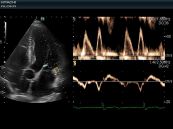

Dưới đây là hình ảnh mặt cắt cạnh ức trái cao trong siêu âm tim bẩm sinh. Mời các bạn tham khảo.

Siêu âm tim là phương pháp chẩn đoán hình ảnh không xâm lấn, an toàn và được sử dụng rất phổ biến trong xác định những bất thường của tim. Dưới đây là hình ảnh về mặt cắt quét dưới mũi ức trục dài trong siêu âm tim. Mời các bạn tham khảo!